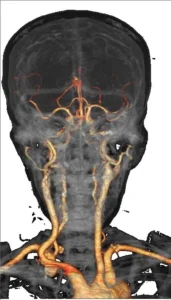

- Das neurovaskuläre System, die kleinen Gefäße der Nierenarterien und der Lungenarterien sind deutlich dargestellt.

• Neurologie: Schlaganfallbeurteilung und vaskuläre Morphologieanalyse.